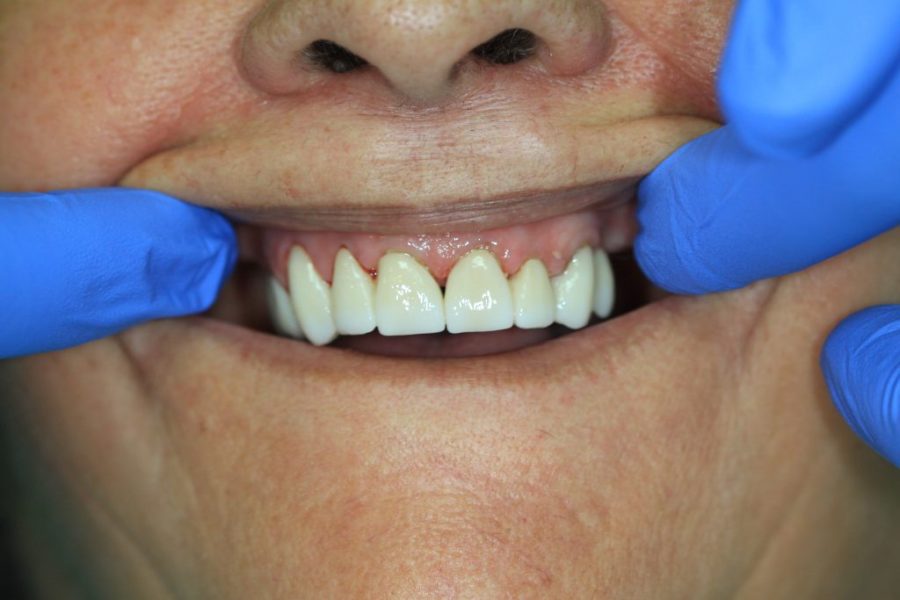

Henry’s Story: A Full Smile Makeover

Henry’s broken teeth were impacting his confidence. With a combination of root canal therapy, laser gum surgery, crowns, and dentures, we restored his smile over four weeks. Now, his family and grandchildren are thrilled with his transformation.